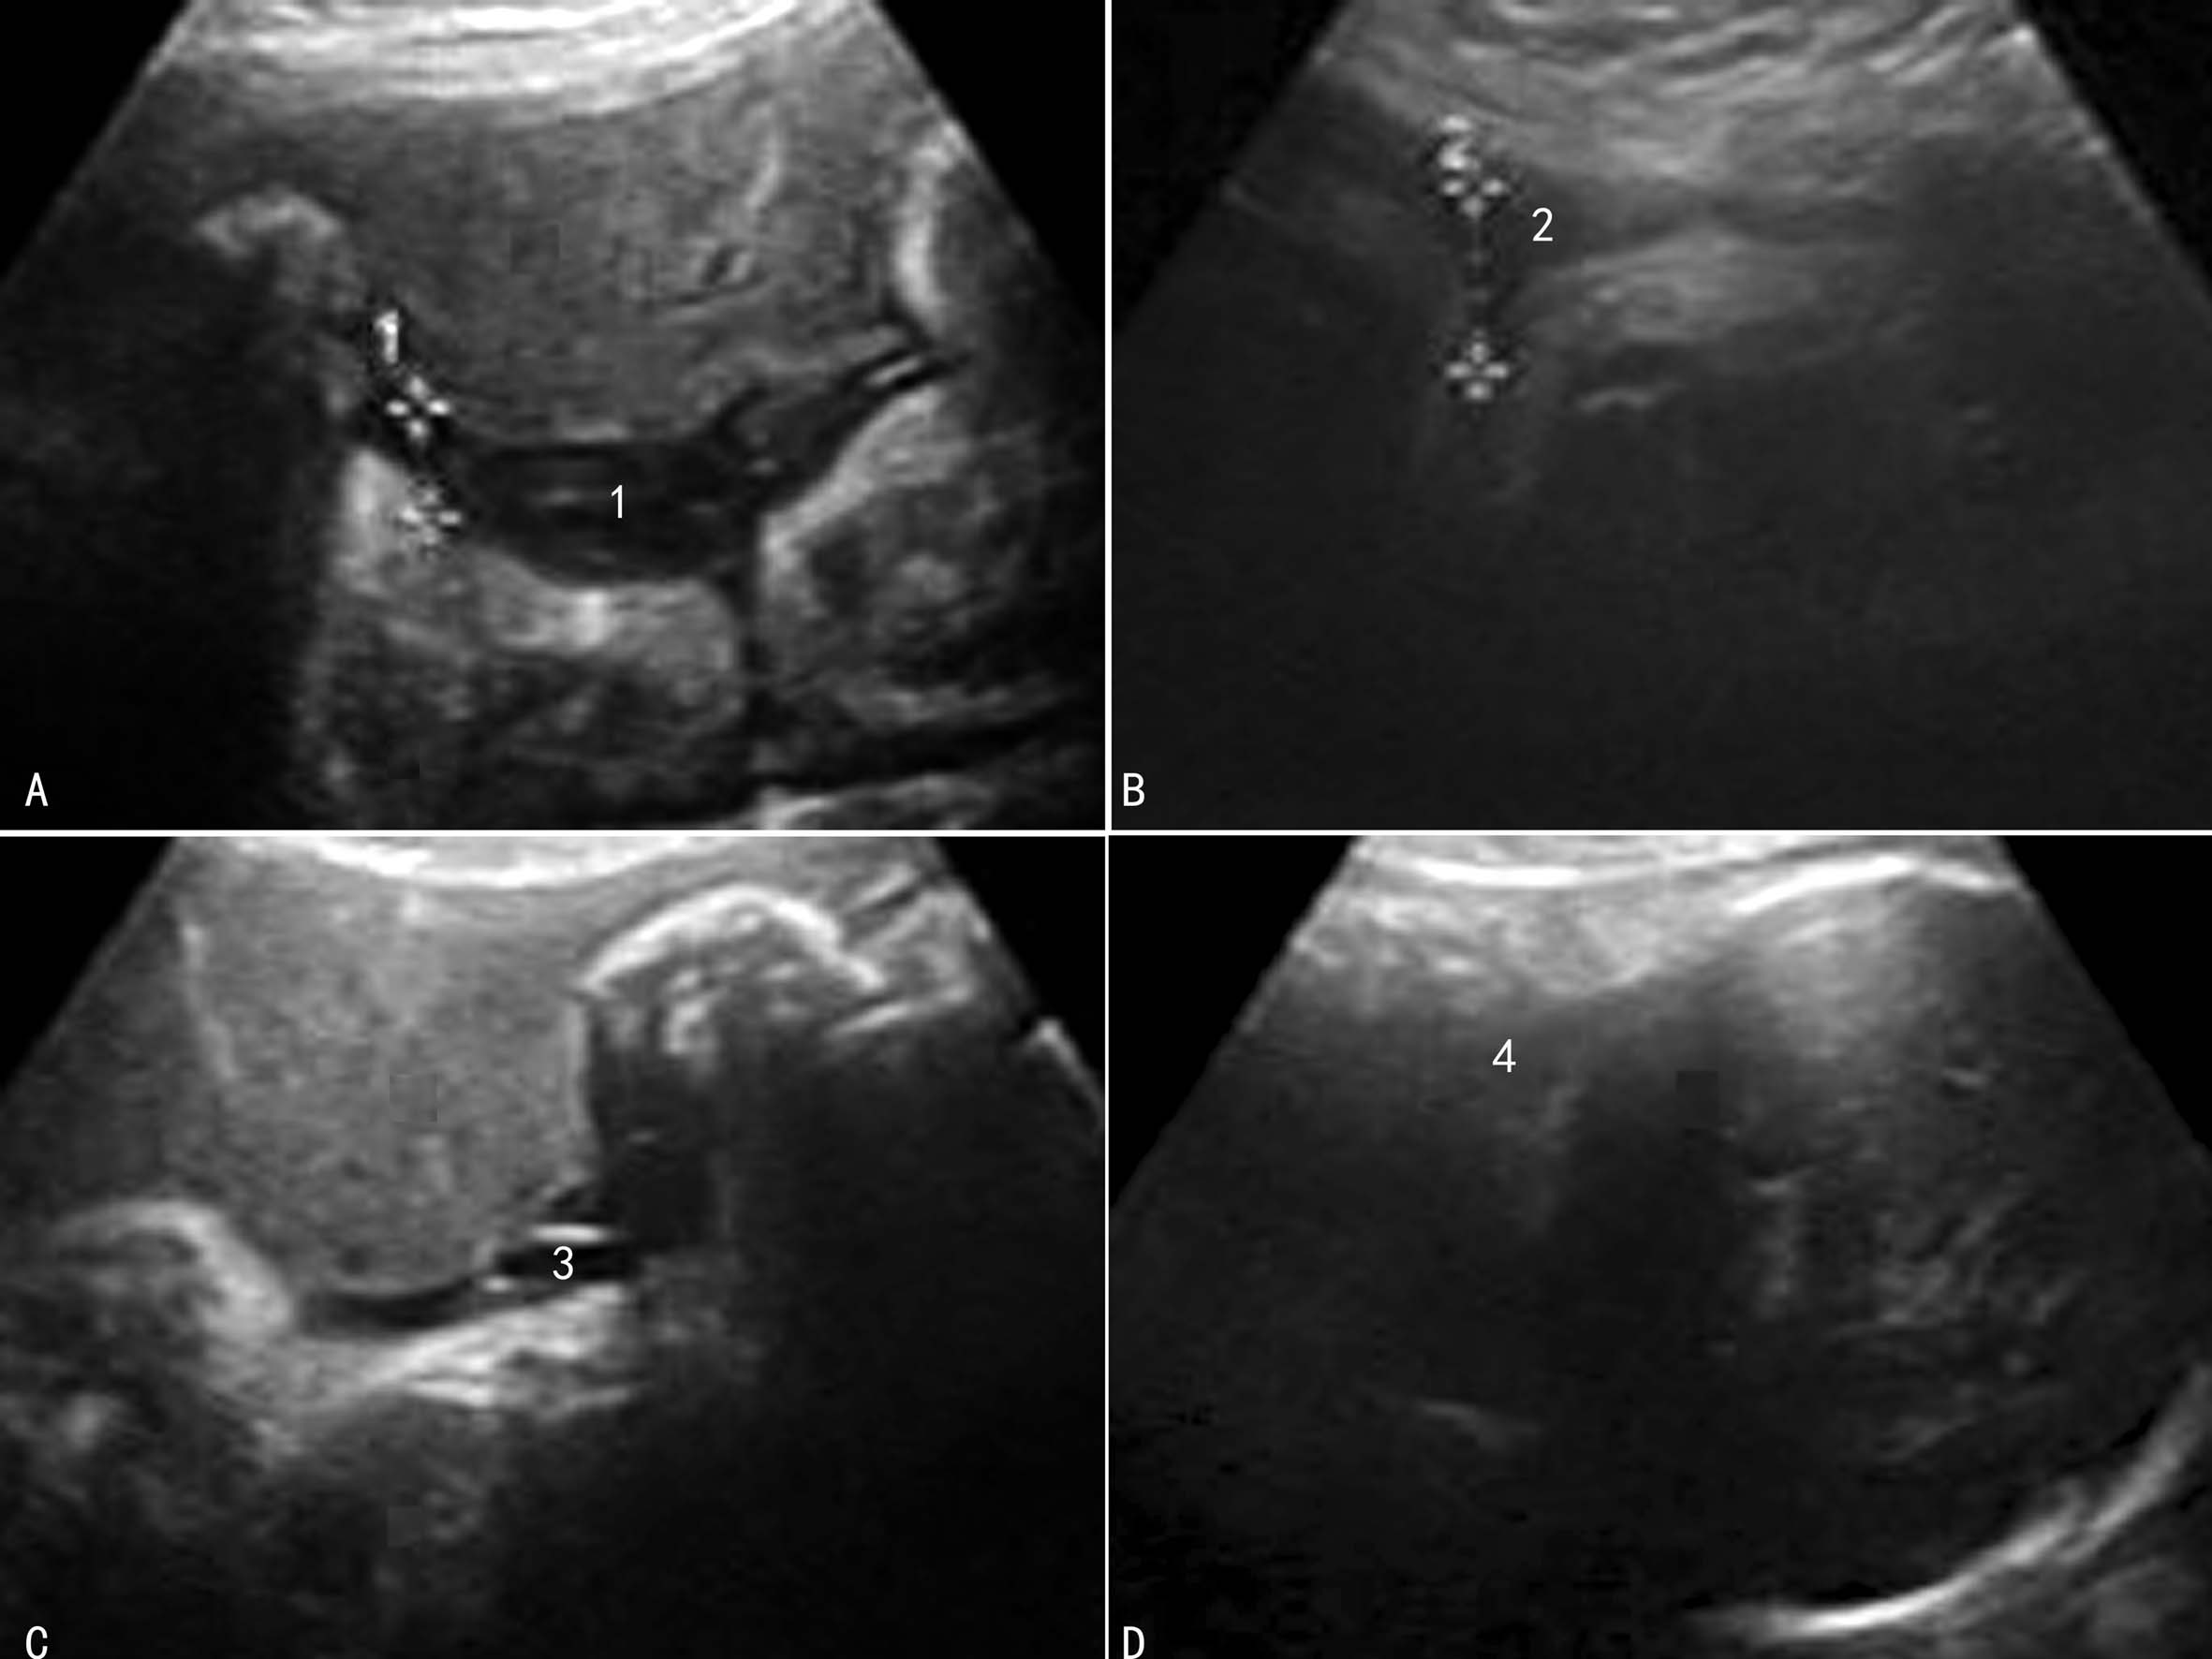

2.中晚期妊娠 比较常用的是测量羊水池内径,当羊水池内径小于3cm时考虑有羊水过少(图1)。一般认为,2cm<羊水池内径<3cm时为轻度羊水过少,1cm<羊水池内径<2cm时为中度羊水过少,<1cm时为重度羊水过少;利用羊水指数评价羊水过少时,羊水指数≤5cm时可诊断为羊水过少,5.1~8cm时为低羊水量或可疑羊水过少(图2)。

图2 羊水指数评价羊水过少